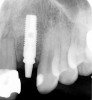

Figure 4  Characterization of the interproximal bone and tooth contacts: A periapical radiograph assists in measuring the distance from bone crest to the adjacent tooth contact points for missing tooth No. 8. The mesial bone crest to the adjacent tooth contact distance is < 5 mm, while the distal bone crest to adjacent tooth contact distance is > 6 mm (Fig 4). One-year following implant placement, conservation of these dimensions is revealed (Fig 5). The clinical photograph (Fig 6) of the lateral incisor adjacent to tooth No. 8 implant crown demonstrates that the absence of distal interproximal (papilla) fill related to the observed bone crest to contact distance exceeds 6 mm.

Figure 4

Figure 5  Characterization of the interproximal bone and tooth contacts: A periapical radiograph assists in measuring the distance from bone crest to the adjacent tooth contact points for missing tooth No. 8. The mesial bone crest to the adjacent tooth contact distance is < 5 mm, while the distal bone crest to adjacent tooth contact distance is > 6 mm (Fig 4). One-year following implant placement, conservation of these dimensions is revealed (Fig 5). The clinical photograph (Fig 6) of the lateral incisor adjacent to tooth No. 8 implant crown demonstrates that the absence of distal interproximal (papilla) fill related to the observed bone crest to contact distance exceeds 6 mm.

Figure 5

Figure 6  Characterization of the interproximal bone and tooth contacts: A periapical radiograph assists in measuring the distance from bone crest to the adjacent tooth contact points for missing tooth No. 8. The mesial bone crest to the adjacent tooth contact distance is < 5 mm, while the distal bone crest to adjacent tooth contact distance is > 6 mm (Fig 4). One-year following implant placement, conservation of these dimensions is revealed (Fig 5). The clinical photograph (Fig 6) of the lateral incisor adjacent to tooth No. 8 implant crown demonstrates that the absence of distal interproximal (papilla) fill related to the observed bone crest to contact distance exceeds 6 mm.

Figure 6